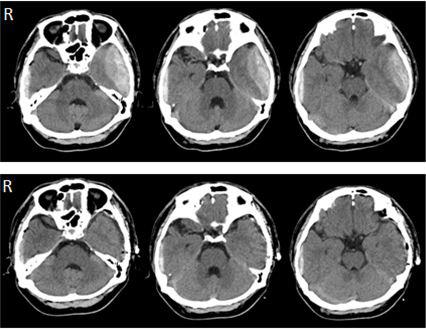

Bilateral Acute Traumatic Epidural Hematoma Due to Coup and Contrecoup Head Injury: a Case Report and Review of the Literature

Koichi Miki